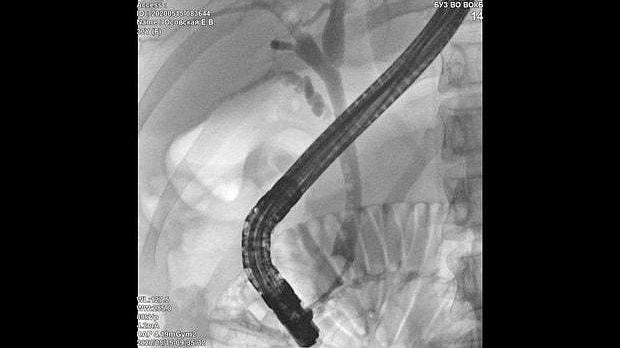

Здравствуйте. Пациентка, 32 года. Поступила на хирургическое отделение с диагнозом ЖКБ: холедохолитиаз. По данным МРТ: ЖКБ, множественные мелкие конкременты холедоха. При дуоденоскопии выявлено наличие вклиненного конкремента большого дуоденального сосочка. Выполнена прекатсфинктеротомия, получено 3 конкремента, диаметром около 0.4-0.5 см. Далее канюляция холедоха проволочным папиллотомом, выявлены многочисленные конкременты холедоха. Выполнена литоэкстракция ревизионным баллоном (на последнем фото окклюзионная холангиография - в просвете холедоха не конкременты, а пузырьки воздуха)).